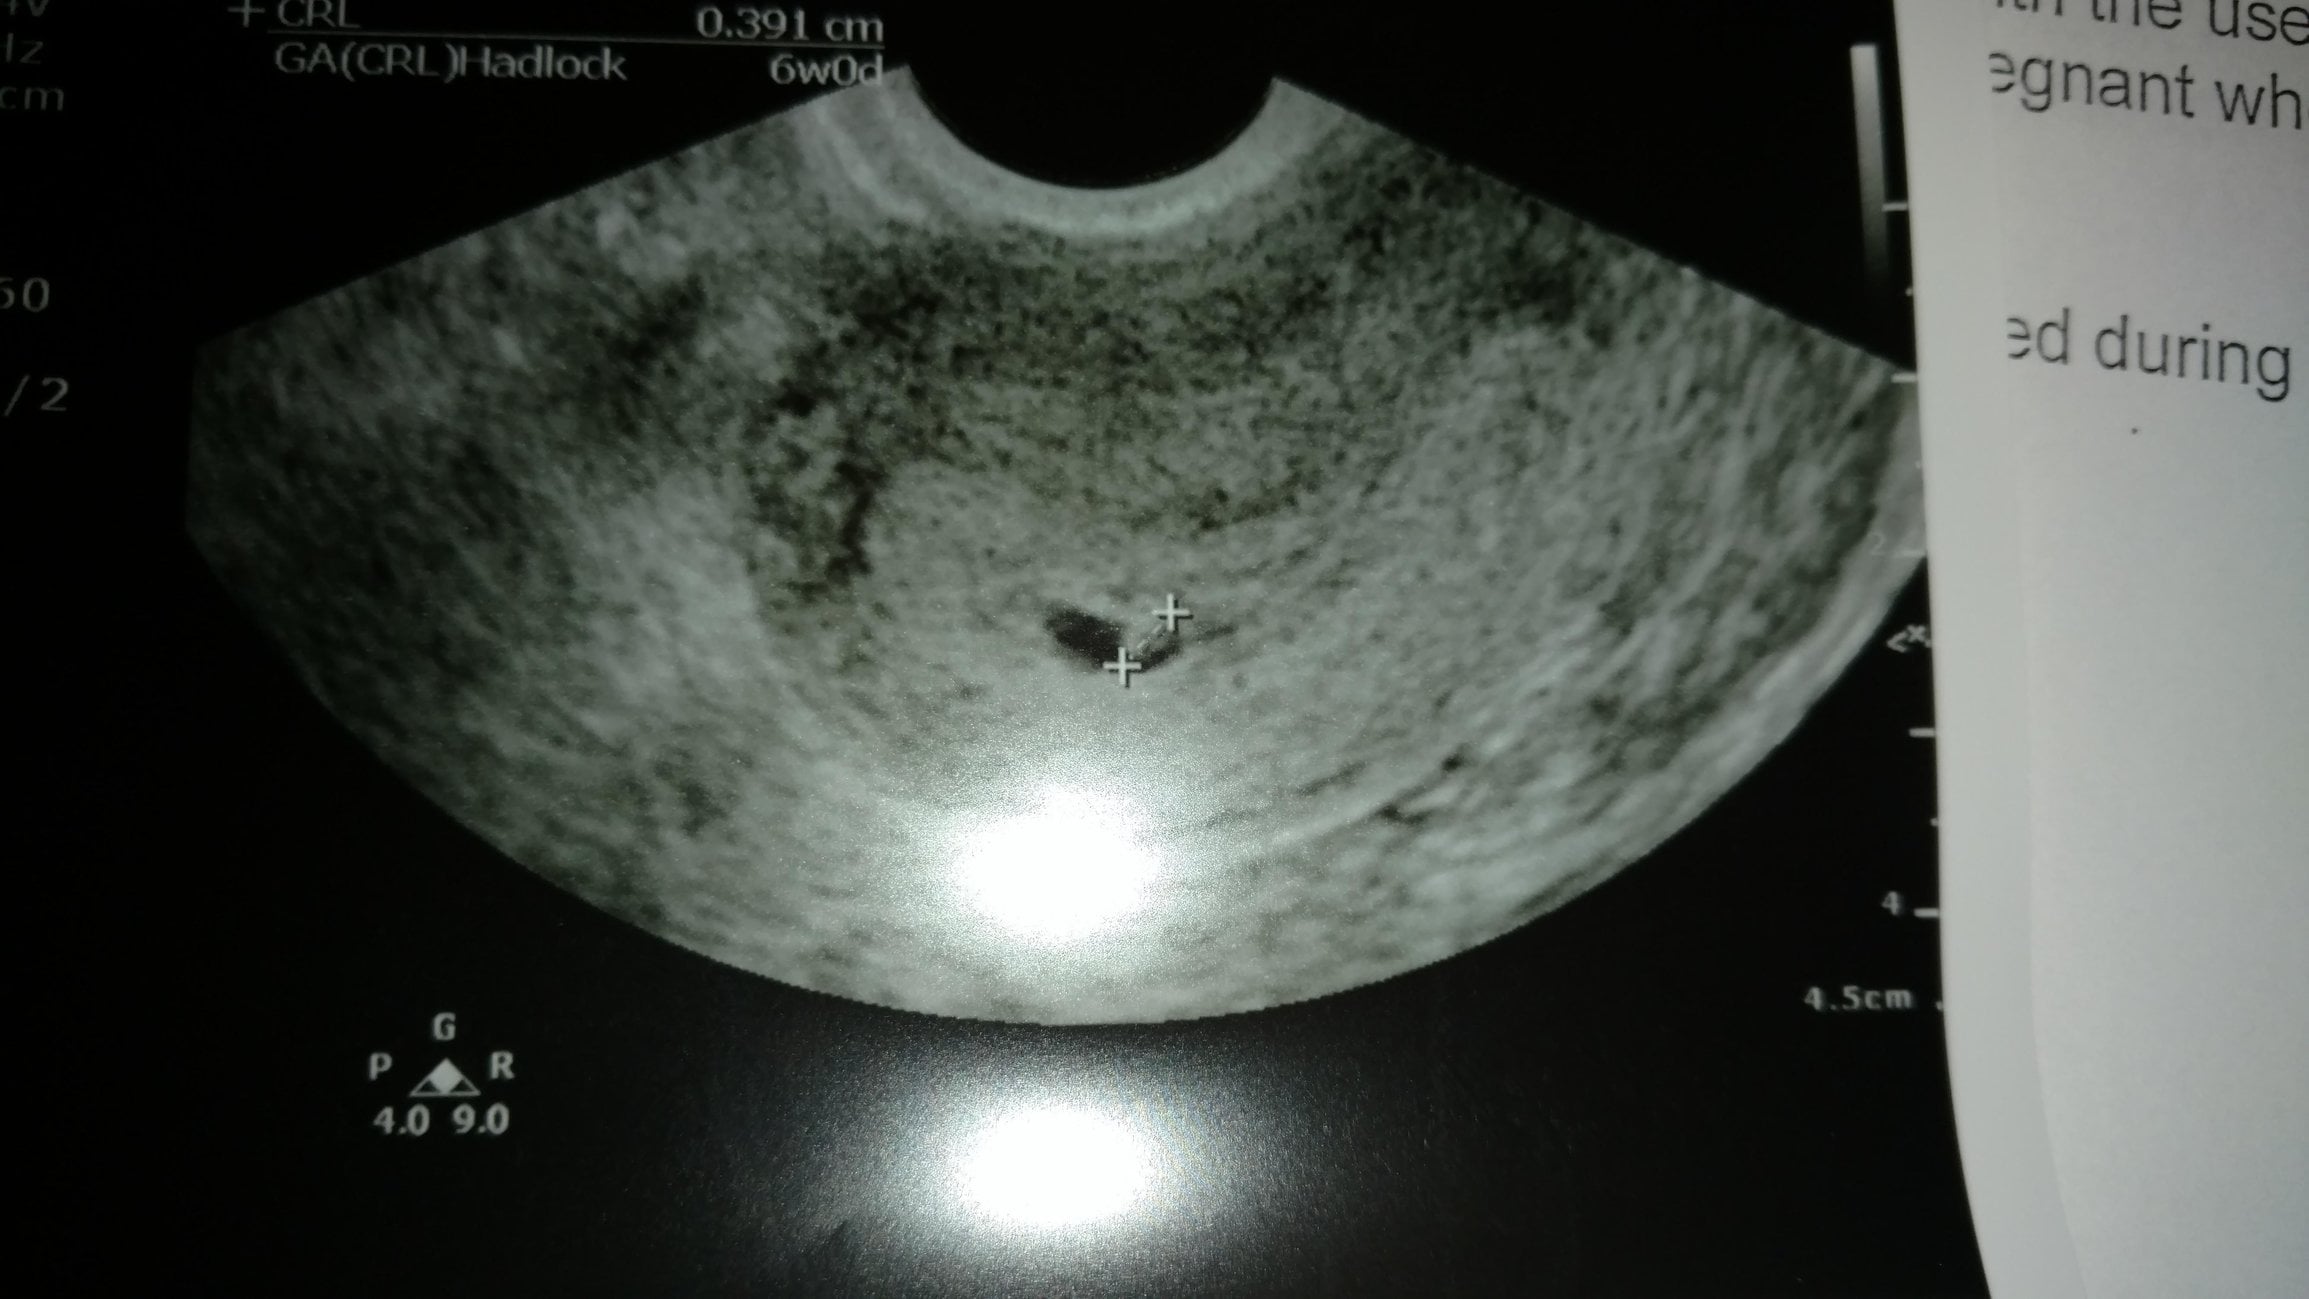

How far along are you? According to LMP 6+4 according to US 6+0

How are you feeling? Physically I'm feeling tired and the nausea comes and goes. My boobs hurt and I'm getting heartburn again. Mentally, I'm feeling better today now that I've seen my baby.

Doing anything baby related today? Just taking it easy now. Had an ultrasound this morning.

R/R/R? It was amazing to see my little baby on the ultrasound even tho there wasn't much to see. I am still very nervous but I feel comfortable enough now to start using our nn for baby. "Pez" is measuring 6w0d today and has a heartbeat pumping away at 116bpm. The nurse didn't seem the least bit concerned about Pez measuring a little small so I'm not going to dwell on it. We have another scan in about 2 weeks (Feb 2) and will actually see the RE that day too. She didn't say if we were adjusting our edd so I'm going to just wait for the next scan to figure that out.